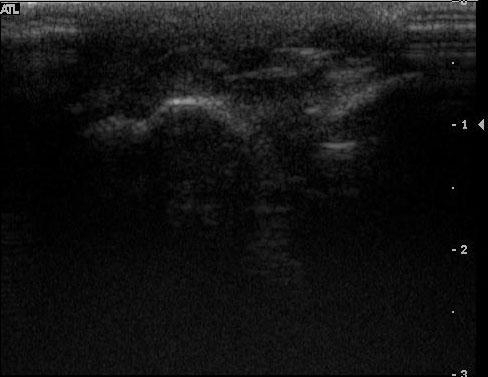

Today’s case comes straight from the ultrasound clinic. This is a 1 year old Pit Bull Terrier with a swelling over the 4th metatarsal bone of the left front limb for one month. Previous surgical exploration was unrewarding. Hint: click on the ‘Show annotated images’ link if you need help identifying the structures.